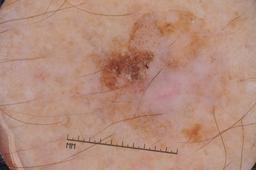

MSK-4

- Name: MSK-4

Description:

Images found based on a search for patients with a personal history, clinical diagnosis, or differential diagnosis of melanoma. All diagnoses confirmed by histopathology.